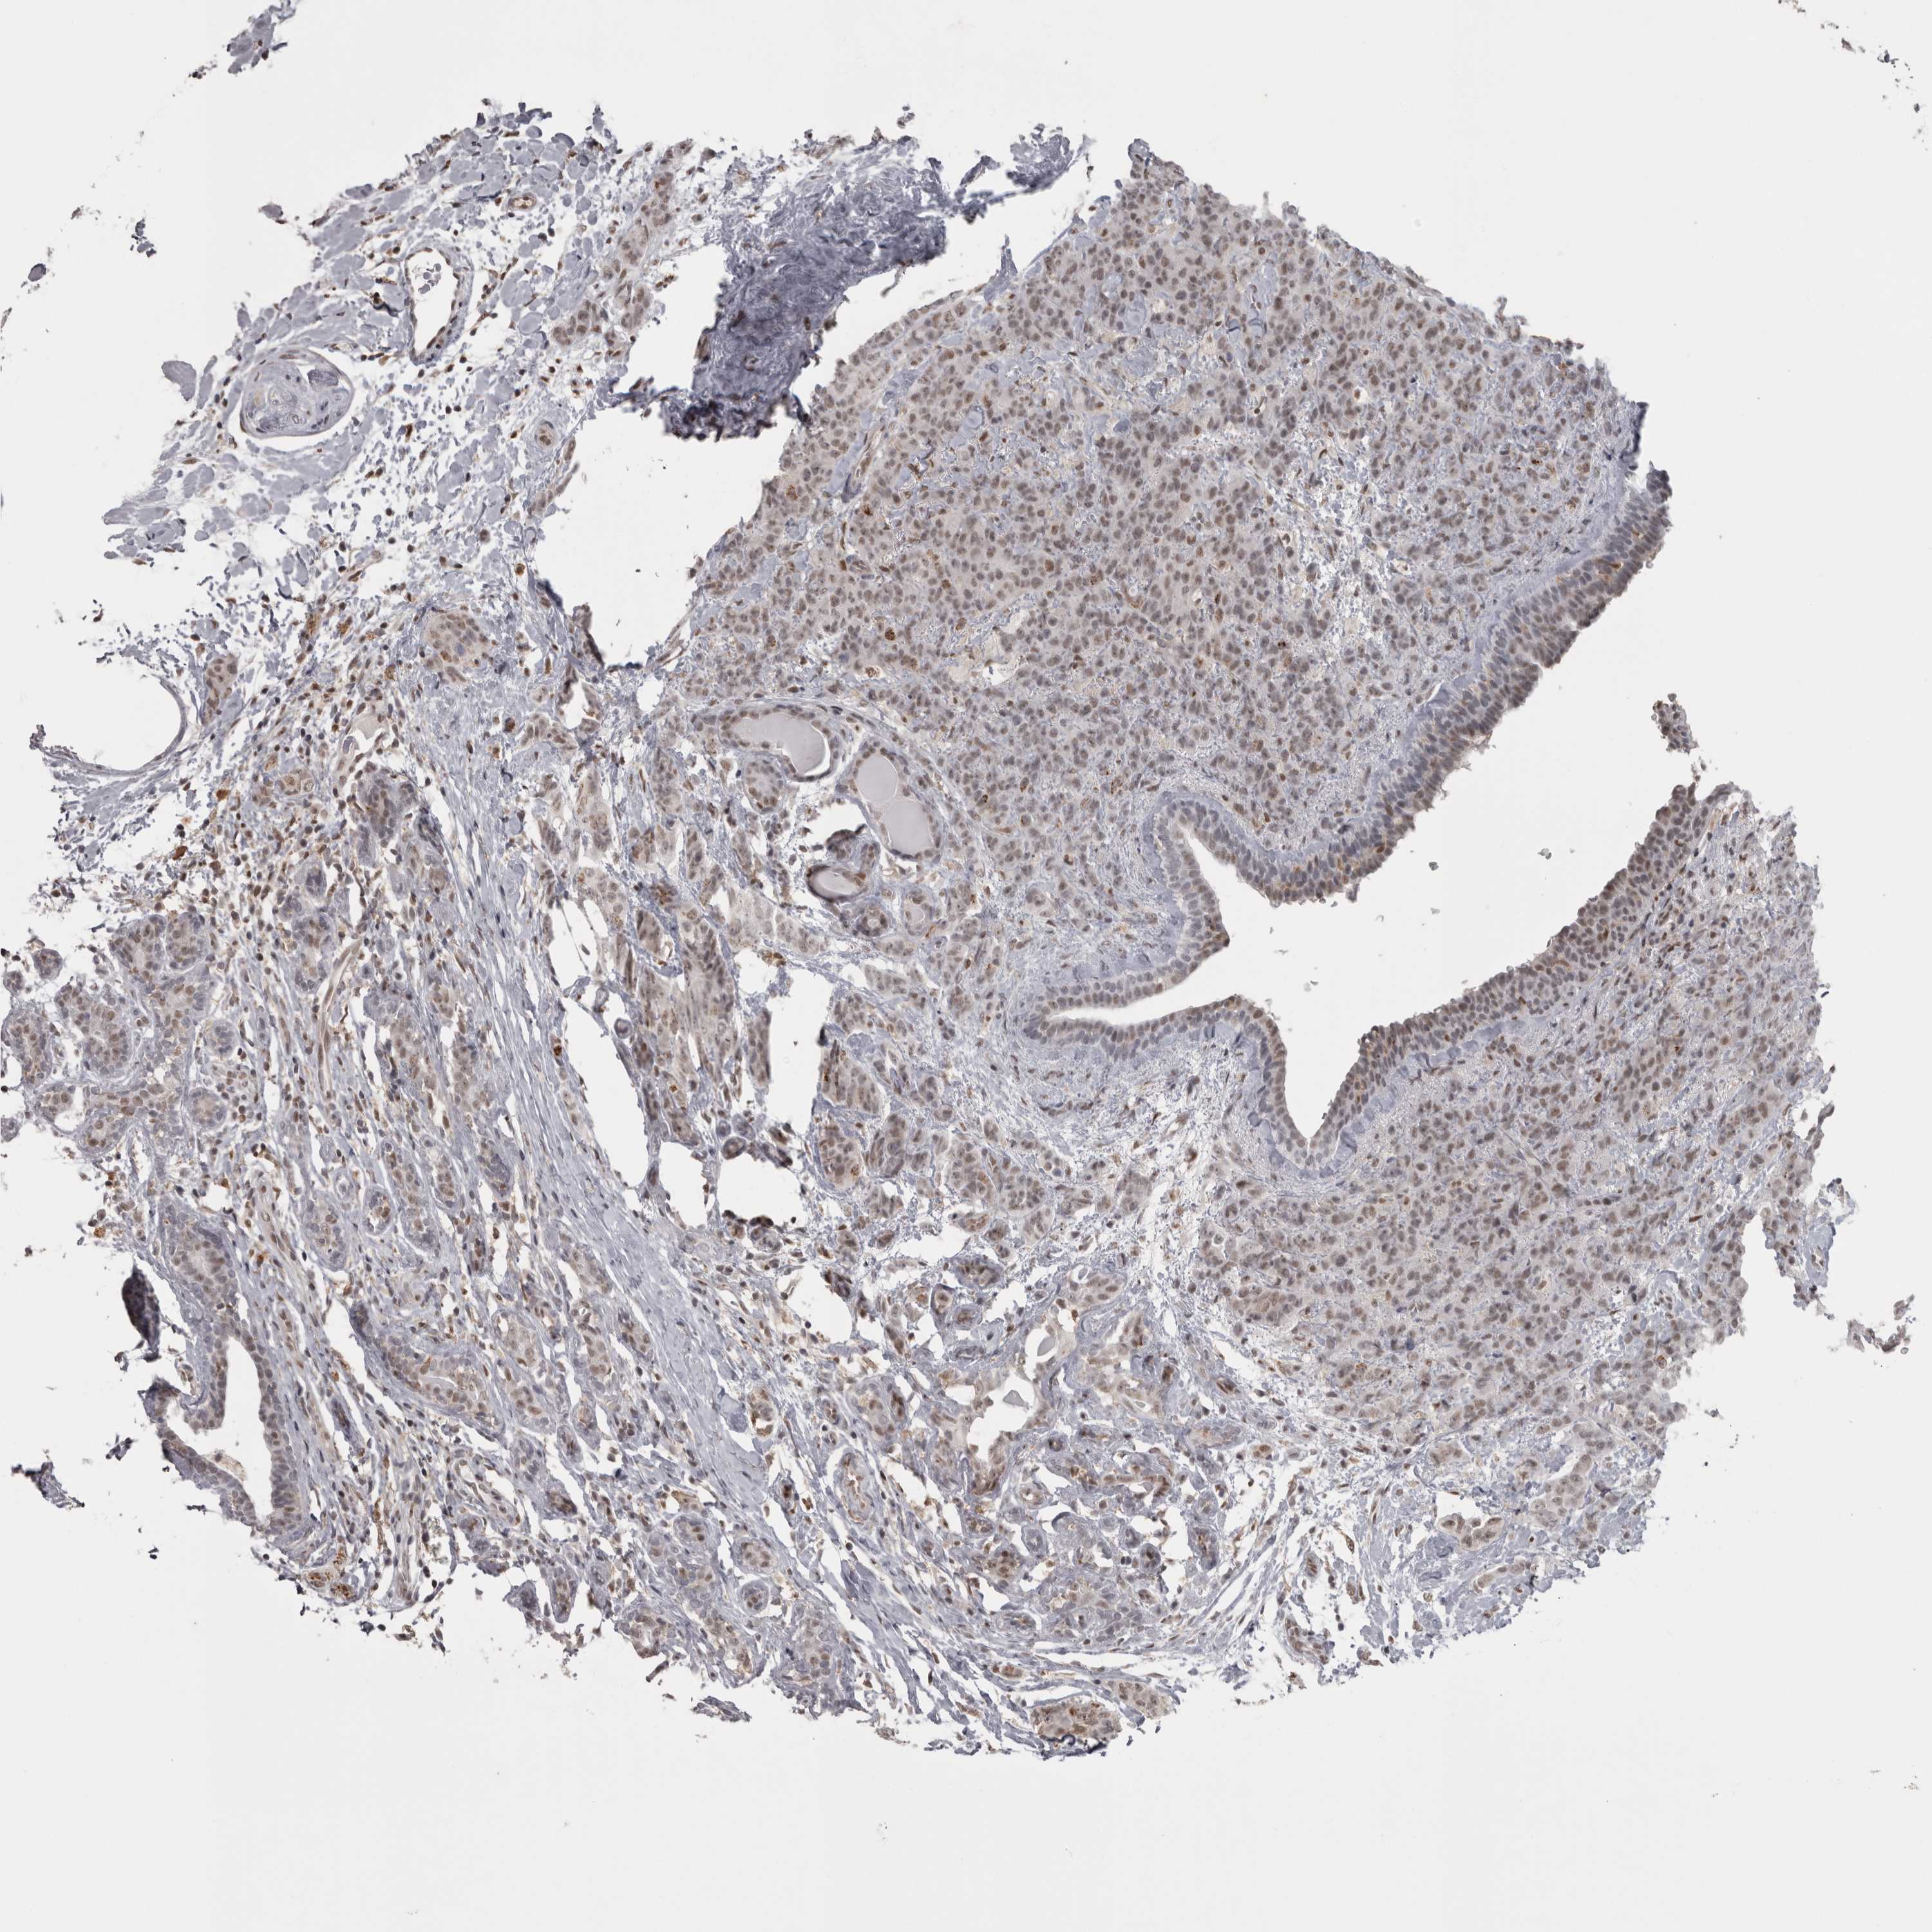

BRCA TCGA BRCA VALIDATION PROTEIN EXPRESSION

ANTIBODIES

AND

VALIDATION